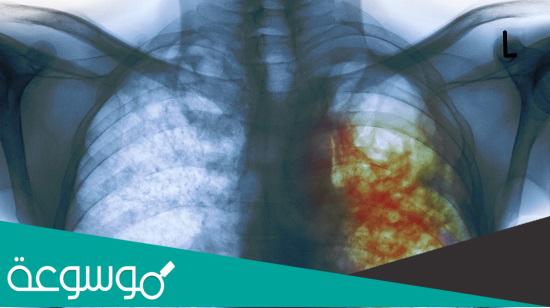

حقائق علمية عن مرض السل بالارقام، يعتبر السل من الأمراض الخطيرة التي يصاب بها الإنسان، ويصنف عالميا أيضا على أنه مرض قاتل، لكن البعض لا يعرف ما هو مرض السل وأسبابه، هذه بعض الحقائق عن مرض السل.

مرض السل مرض خطير ، ويعرف بأنه نقص في جهاز المناعة. تم إحصاء مرضى السل في العالم ، ووجد أن حوالي ثلث سكان العالم مصابون بالسل ، وهذه النسبة ليست صغيرة. أجرت منظمة الصحة العالمية بحثًا في عام 2014 ، ووضعوا استراتيجية لمرض السل خلال السنوات القادمة حتى عام 2030 م هي فترة للحد من انتشار مرض السل ، وخفض معدل الوفيات إلى 90٪ ، وتقليل حدوثه إلى 80٪ حتى عام 2030 م ، وهناك بعض الحقائق عن مرض السل يجب أن نعرفها.